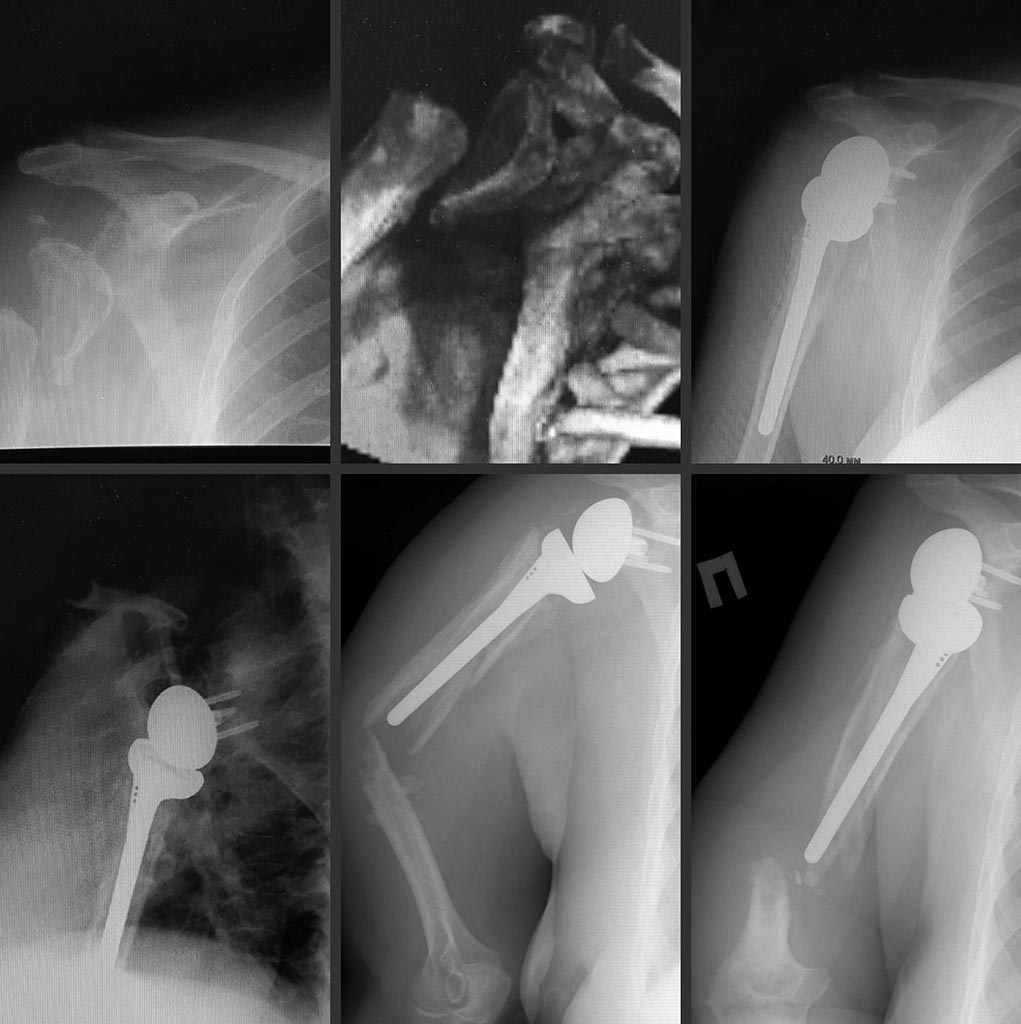

[Ortho] Перипротезный перелом правого плеча

Пациентка 64 года. Оперативное лечение в октябре 2015 года конструкцией

Delta XTEND. В декабре 2015 года падение на правый бок, появление

патологической подвижности в с/3 плеча отмечает с февраля 2016 года, за

медицинской помощью обратилась только в августе.

Отмечается патологическая подвижность в с/3 плеча. Отведение/сгибание в

плечевом суставе 90 гр. Выпадения чувствительности в конечности нет.

1) накостный остеосинтез с фиксацией дистально винтами, проксимально

монокорткально с добавлением серкляжей , иммобилизация 10-12 недель;

2) удаление конструкции, ИМО также с добавлением серкляжей проксимально

и с формированием на конце штифта сферичного спейсера по типу головки,

при условии консолидации реэндопротезировние.